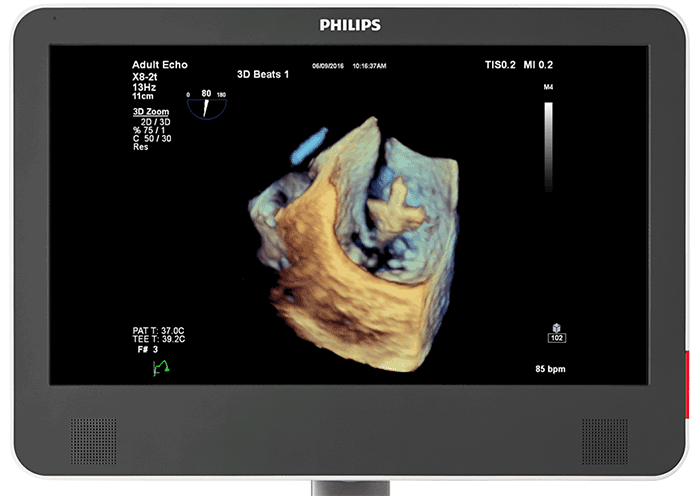

3D photorealistic rendering with virtual light source For improved visualisation of cardiac anatomy in the transthoracic and transesophageal echo, Philips cardiology TrueVue with its virtual light source makes it simpler to visualise the location of defects and comprehend depth within the structures. 90% of clinicians5 who saw the new Philips EPIQ CVx felt that the new TrueVue 3D photorealistic rendering provided improved viewing of anatomical structures, thus increasing clinical confidence.

Designed for next-generation Live 3D TEE The acoustic design of the Philips X8-2t Live 3D transesophageal transducer provides higher frequencies and bandwidth for increased resolution and tissue filling in 2D and Live 3D. It brings true one-beat acquisitions and our highest volume rates in Live 3D and Live 3D colour flow without compromise to image quality. Its handle is designed with a real-time configurable function button allowing for additional functionality while imaging.